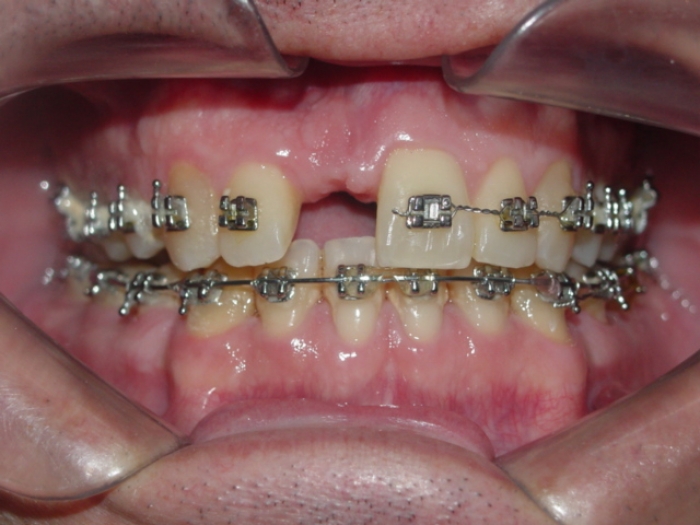

Imagem inicial